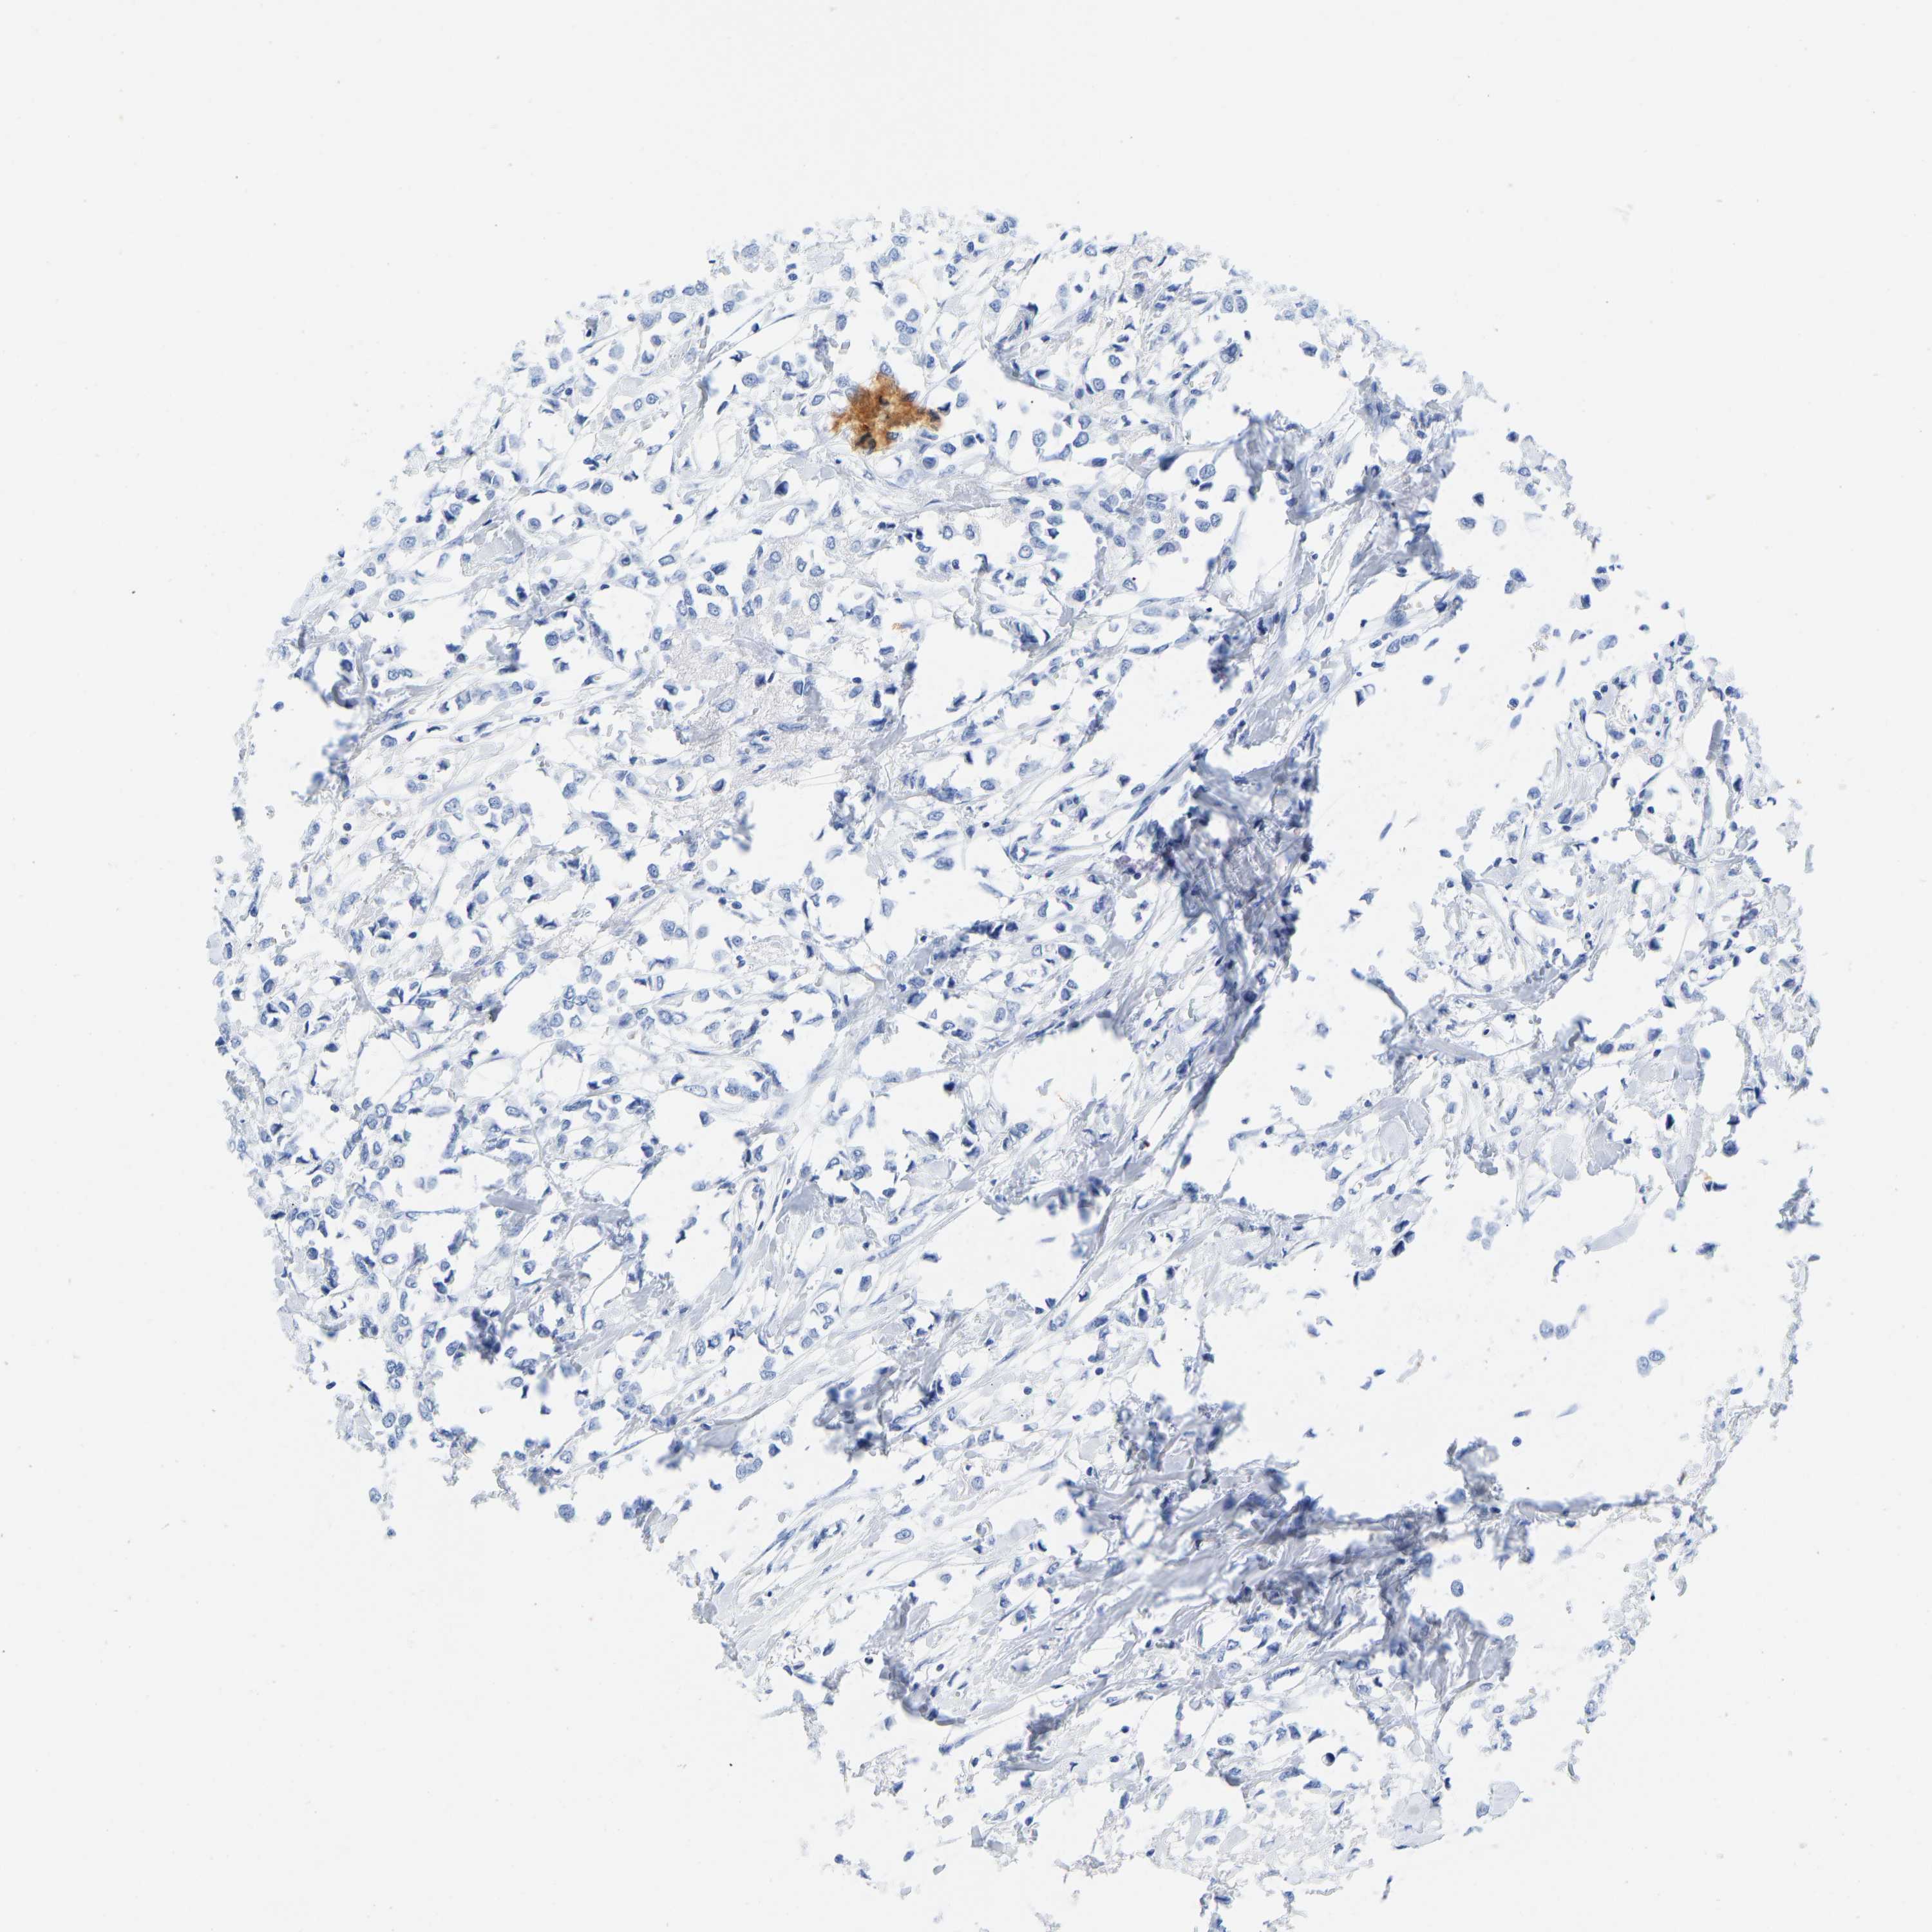

CANCER BREAST CANCER Show tissue menu

BRCA TCGA BRCA VALIDATION PROTEIN EXPRESSION